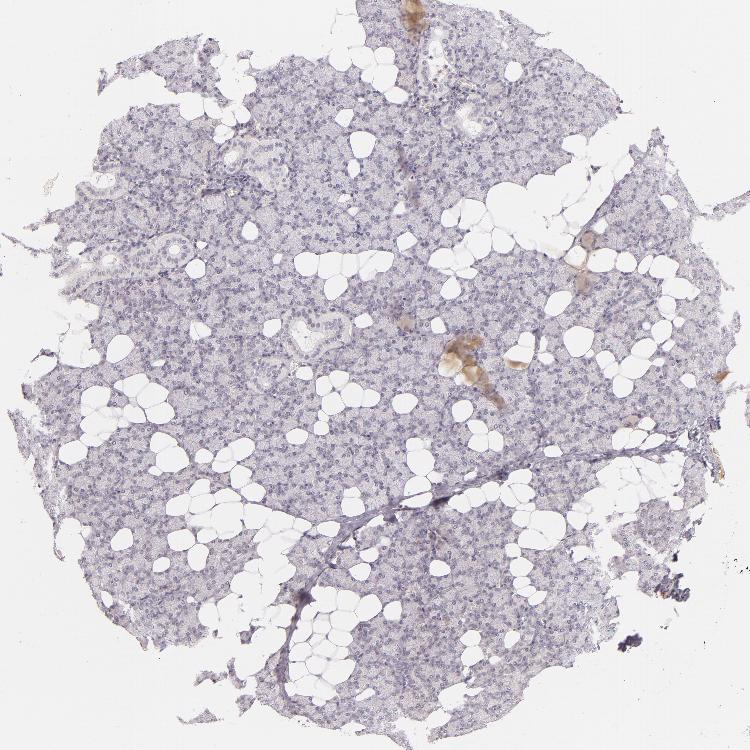

SALIVARY GLAND - Antibody stainingi

Antibody staining in the annotated cell types in the current human tissue is reported as not detected, low, medium, or high, based on conventional immunohistochemistry profiling in selected tissues. This score is based on the combination of the staining intensity and fraction of stained cells.

Each image is clickable and will lead to virtual microscopy that enables deeper exploration of all samples and also displays staining intensity scores, fraction scores and subcellular localization as well as patient and tissue information for each sample.

Antibody HPA001302Antibody HPA005688Antibody CAB002047

Glandular cells MediumHighLow